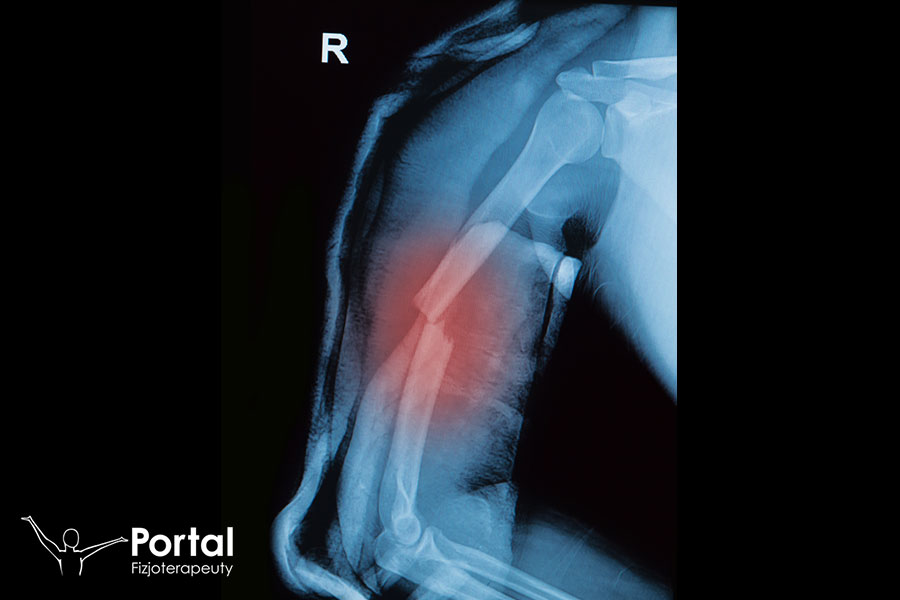

Gips wiszący Caldwella

Gips wiszący Caldwella wciąż znajduje zastosowanie w ortopedii i rehabilitacji, szczególnie do stabilizacji złamań kości ramiennej. Warto wiedzieć, że po